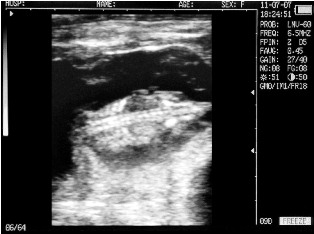

Uterine horn heifers